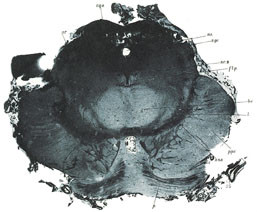

Fotografiet medførte imidlertid metodiske problemer. Figur 10 er en illustrasjon vedrørende nervesystemets anatomi, basert på et fotografi (13). Mikrosnittene ble projisert på en hvit flate i mørkerommet. Når innstillingen var tilfredsstillende, ble innstillingsplaten erstattet med lysfølsomt materiale og bildet ble belyst. Men når bildet var fremkalt, kunne det vise seg at det var noe som så ut som feil. Det kunne være feil som skrev seg fra preparatet og feil som skyldtes den fotografiske teknikken. Hva var da sannheten? Kunne man tillate seg å retusjere? Filmmaterialets varierende fargefølsomhet var også en faktor som kunne medføre at fotografiet ikke nødvendigvis gav den informasjon man hadde tenkt at det skulle gi, selv om det i teorien skulle være en gjengivelse fri for menneskelig subjektivitet. Figur 10 er for øvrig en slags mellomteknikk mellom grafikk og fotografi, fotogravyr, idet bildet er overført fotografisk til en kobberplate som så ble etset.